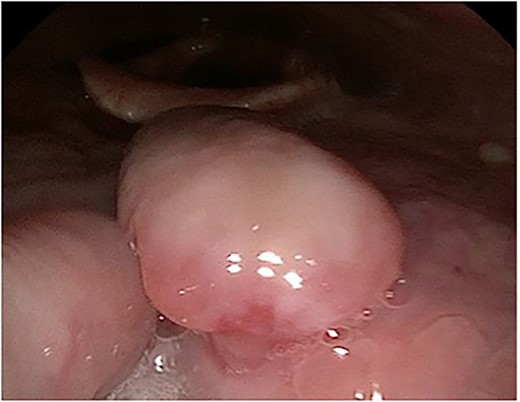

A 63-year-old male with a medical history of hypertension and progressive dyspnoea on exertion, underwent a computed tomography (CT) angiogram for the workup of a pulmonary embolism. There was an incidental finding of a 12-cm left renal neoplasm (Fig. 1), extensive metastatic nodal abdominal disease and bilateral metastatic pulmonary disease (T3 N2 M1). He was discussed at the Urology multidisciplinary team meeting (MDT) and commenced on Sunitnib, given the dissemination of disease. Repeat imaging showed a significant reduction in size of the pulmonary metastasis. Following which, he underwent a cryo-reductive nephrectomy that confirmed a clear cell RCC 102 mm, Grade 3. Development of a tongue lesion after a year warranted Otorhinolaryngology input. Clinical assessment with flexible nasendoscopy depicted a 0.5 cm by 0.5 cm pedunculated lesion on the midline of the tongue (Fig. 2). A biopsy under local anaesthetic confirmed a clear cell RCC (Fig. 3) that was positive for AE1/AE3, Vimentin (Fig. 4) and EMA. Further CT imaging, 1 month after the biopsy confirmed left hilar nodule progression from 2.3 to 3 cm. The medical oncology MDT recommended commencing Nivolumab. Following recurrent bleeding from the tongue, radiation to the area was determined to be the best treatment modality. The patient is still clinically well and tolerating oral intake with no significant large bleeds to date. Regular medical oncology, radiation oncology, urology and Otorhinolaryngology follow-up is ongoing, however, the prognosis is poor with such disseminated disease and the primary focus is on minimising morbidity.

Immunohistochemical staining confirming Vimentin positivity and the presence of malignant RCC over a benign Oncoytoma.

The main histological subtypes of RCC are clear cell, papillary, chromophobe, collecting duct carcinoma, medullary carcinoma and unclassified [6]. Distinction between clear cell salivary tumours and RCC should be made prior to treatment, as histologically, this can be difficult to perform on standard light microscopy. A strong reaction to Vimentin will confirm this on immunohistochemical staining [7]. To find an RCC metastasis on the tongue is rare; the oral cavity consists of the anterior two thirds of the tongue, the lips, the floor of mouth, hard palate, buccal mucosa, maxillary and mandibular alveolus and the retro molar trigone. One of the theories regarding metastatic spread of RCC is that Batson’s venous plexus extends from the skull to the sacrum. This valveless system theoretically offers less resistance to the spread of tumour emboli, especially when there is an increase in intrathoracic and intra-abdominal pressure, allowing retrograde flow by-passing the pulmonary filters [8].